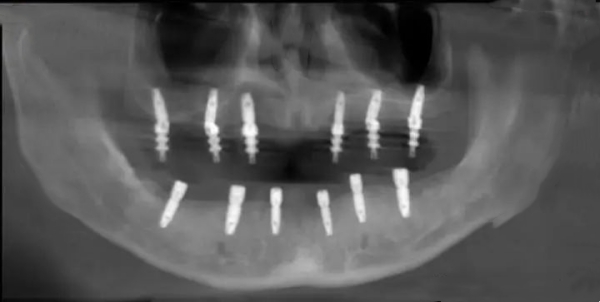

5、半口和全口種植牙費(fèi)用

半口種植牙價(jià)格一般在2萬元起,而全口種植牙價(jià)格通常在4萬元到10萬元之間。

2、數(shù)字化種植技術(shù)

部分分院引入數(shù)字化種植技術(shù),可以通過口腔CT規(guī)劃種植位置,提高種植牙精度。